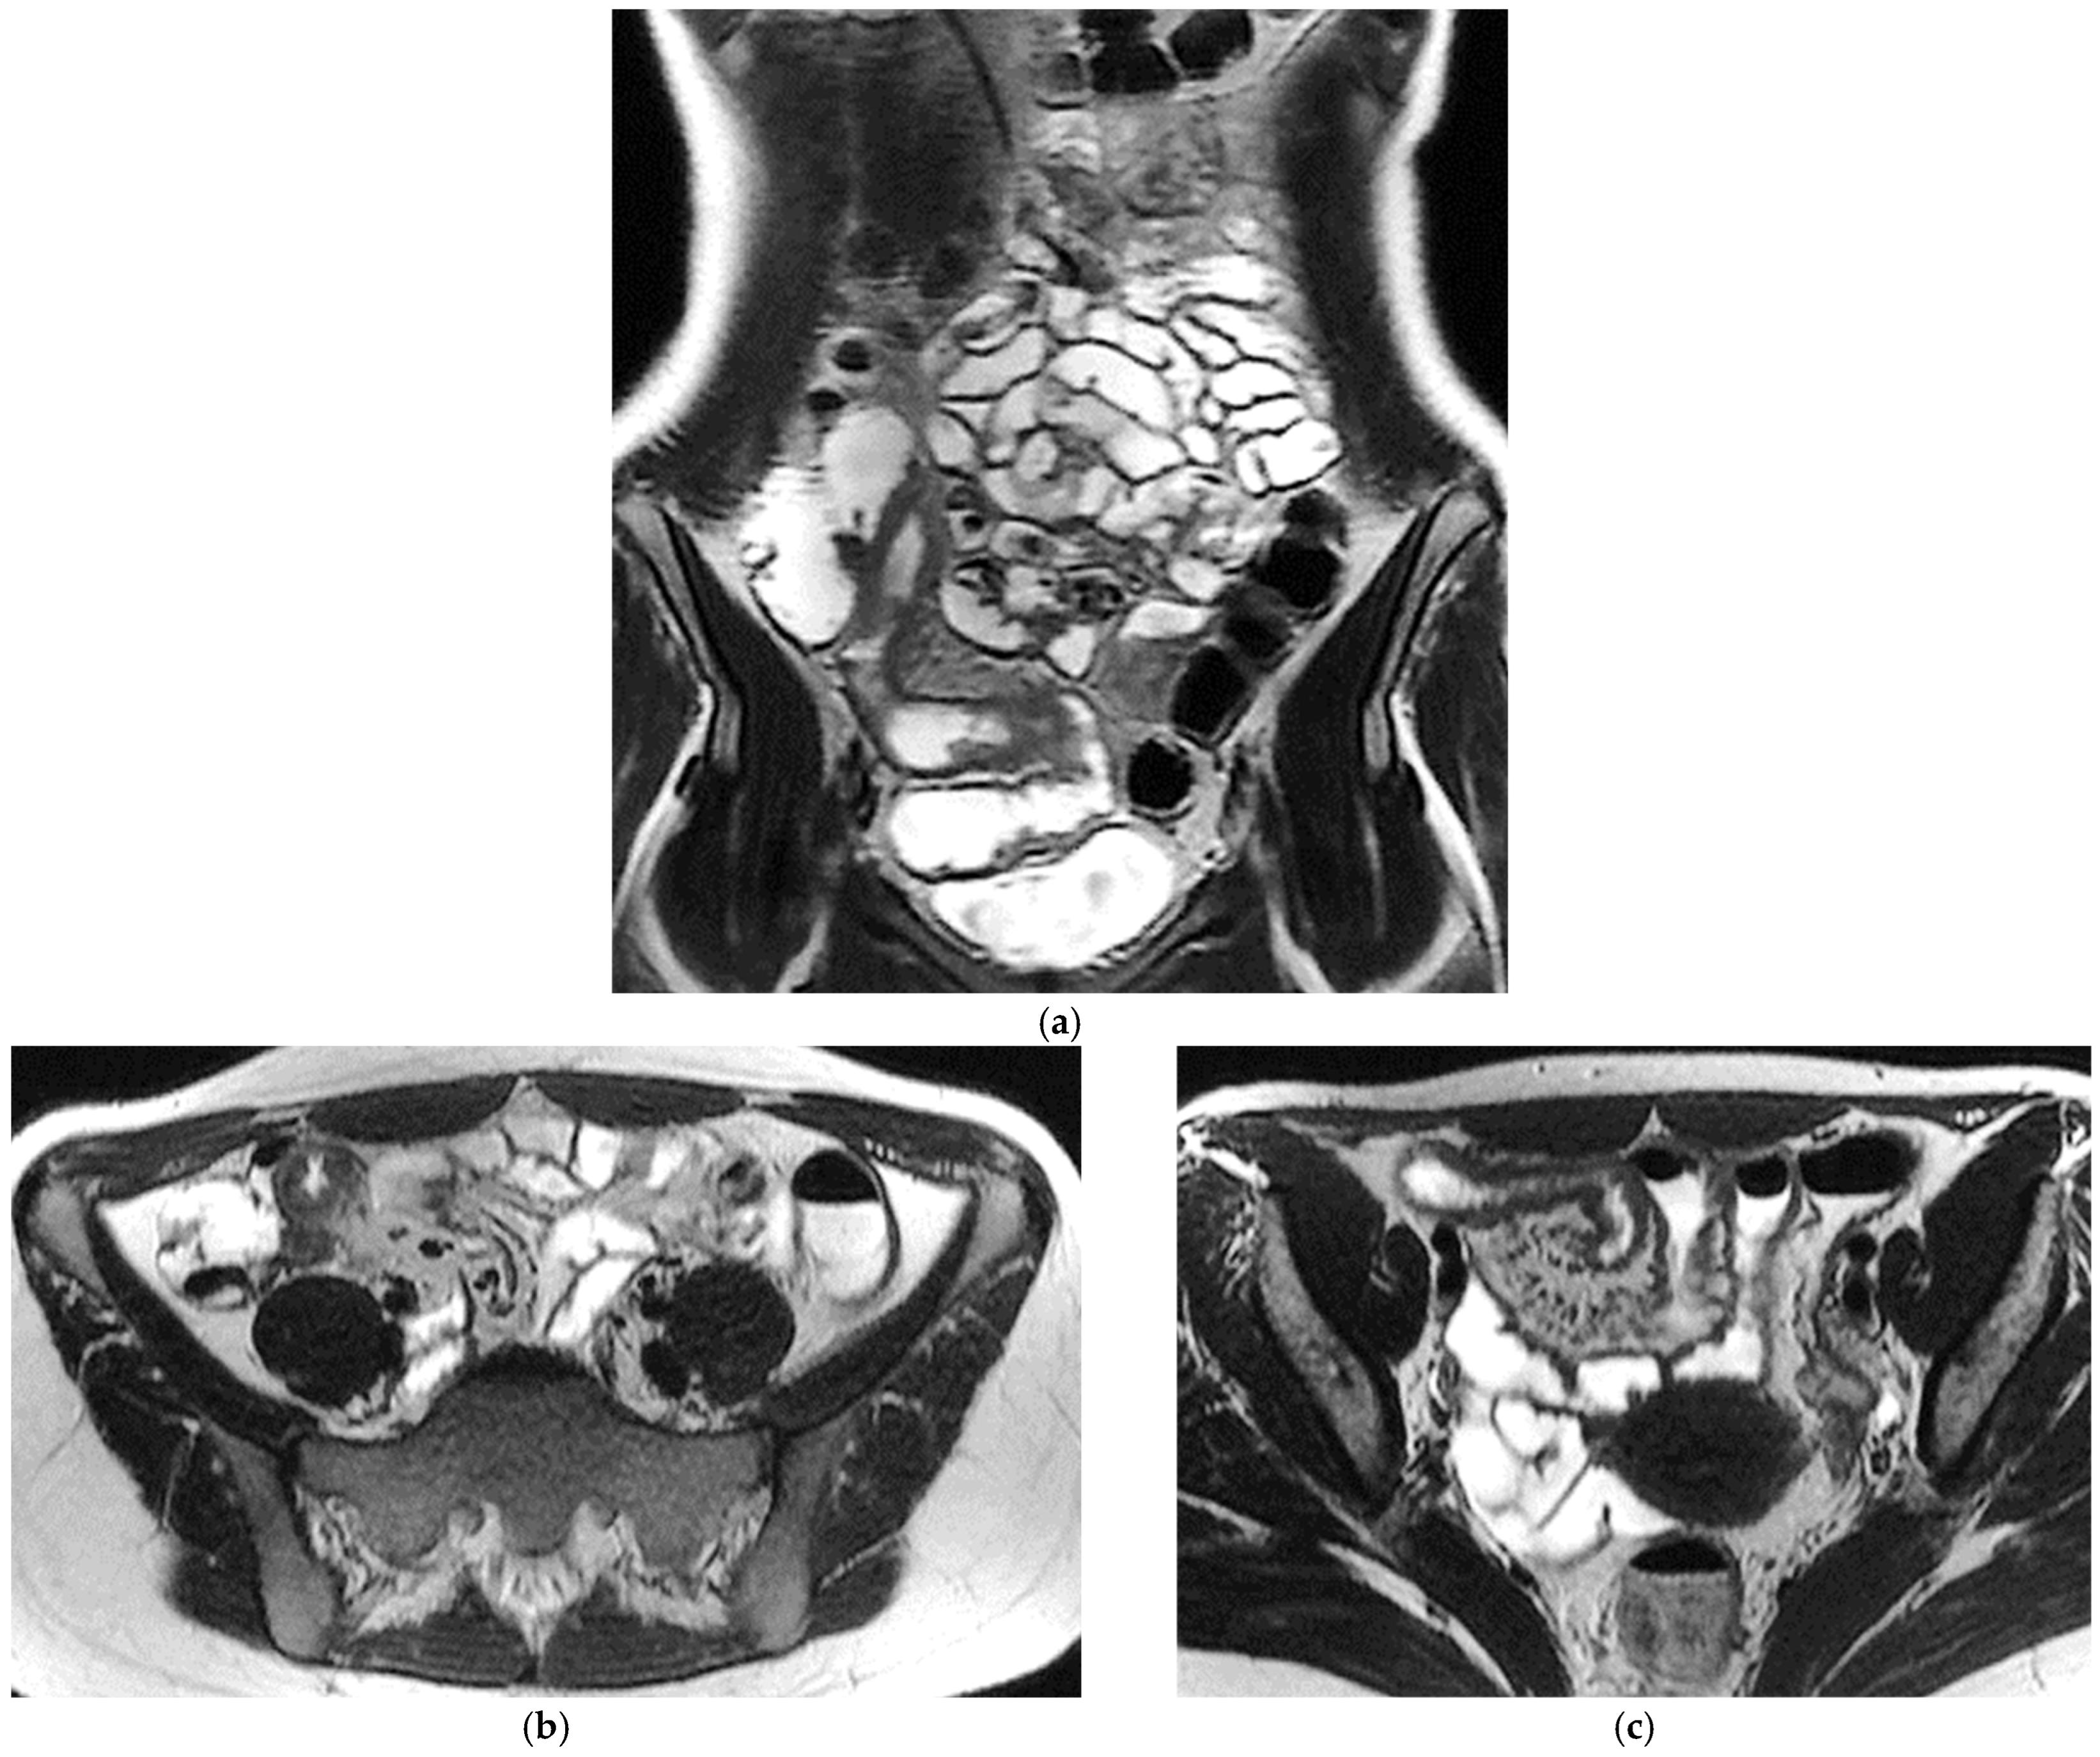

CT Enterography (CTE) is a dedicated technique that can be performed using either neutral (water macrogol solutions) or positive (iodinated) oral contrast for optimal luminal distention, thereby enhancing the modality’s utility in elective outpatient evaluation, shown on Figure 4 and Figure 5. CTE performed with positive oral contrast improves visualization of the entire small bowel lumen and interloop relationships, and is particularly useful in complex disease associated with adhesions and fistulas (Figure 4a–d and Figure 5a–d). On the other hand, CTE performed with negative oral contrast enables assessment of mucosal hyper-enhancement, wall thickening, and inflammatory changes (Figure 5). However, although CTE can approximate much of the mural and extramural information obtained with MRE, it lacks the functional imaging capabilities of MRI and cannot distinguish with confidence between inflammatory and fibrotic strictures. For this reason, CT is generally reserved for situations in which MRE is unavailable or contraindicated, or when specific luminal abnormalities, such as unexplained focal thickening or suspected small-bowel polyps, require rapid clarification [20,21,39,40,41].

Figure 4.

(a,b) Axial CT scan in the venous phase after administration of positive oral contrast medium (Gastrografin) showing thickened terminal ileum in a 65-year-old patient with Crohn’s disease. (c,d) Coronal CT scan in the venous phase after administration of positive oral contrast medium (Gastrografin) showing thickened terminal ileum (arrows) in a 65-year-old patient with Crohn’s disease.

Figure 5.

(a,b) Coronal CT scan in the venous phase after administration of negative oral contrast medium (PEG-solution) showing thickened ileal loops (arrows) in an 85-year-old female patient with Crohn’s disease. (c,d) axial CT scan in the venous phase after administration of negative oral contrast medium (PEG-solution) showing thickened ileal loop (arrows) in an 85-year-old female patient with Crohn’s disease.